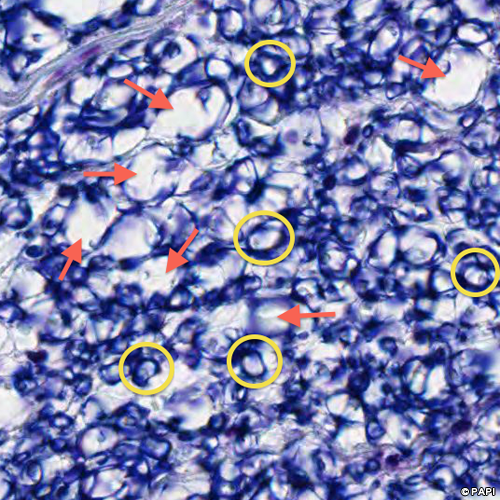

• 軸索(大径線維)を○で囲んでいる。軸索の周りが白く抜けている部分(矢印)は、髄鞘が存在する部分である)(Bodian染色では染まらない)。